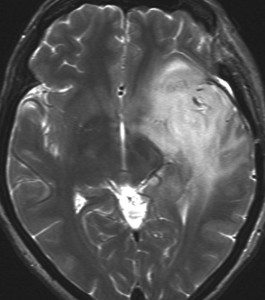

ぼーっと白くみえるのが星細胞腫です。この腫瘍はグレード2の腫瘍でした。実際にはこのMRIで白くにじんで映って見える領域より,腫瘍はさらに広い範囲に浸潤して広がっています。すごく大きいのですが,これでも無症状です。びまん性星細胞腫は脳の中にしみ込むように発育するので治療が難しいのです。手術でこれを全部とることはできません。浸潤性グリオーマ infiltrative gliomaの典型例です。

でも逆に,かなり限局性で正常脳との境界がはっきりしていて,手術で完全摘出できるびまん性星細胞腫もあります。上の例とは,病理診断が同じとは思えないくらいです。こういうのを限局性グリオーマ localized gliomaといいます。

両者ともにIDH1変異のある例でした。IDH変異型 びまん性星細胞腫 グレード2といってもかなり臨床像と治療法,予後に異なりがあります。